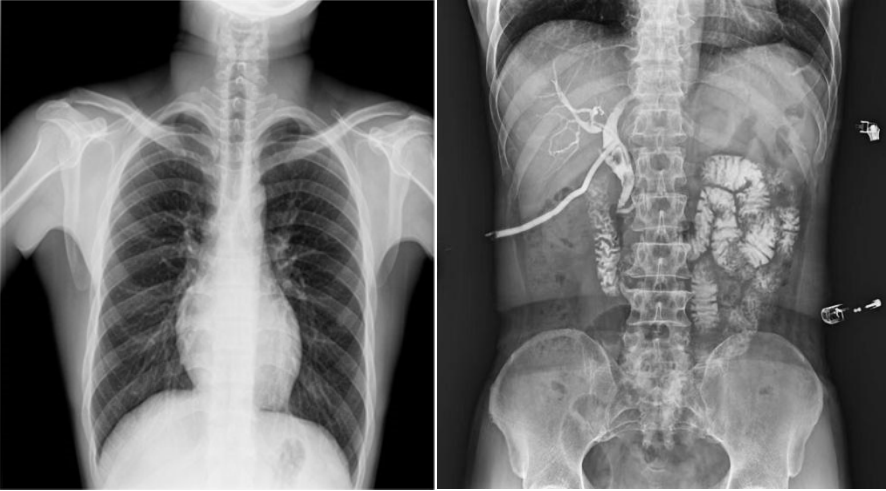

高幀動(dòng)態(tài)平板,快速獲得高清影像。線性探測(cè)平面,圖像無(wú)畸變、無(wú)失真;17×17英寸超大視野,透視幅面大,一幅畫(huà)面即可覆蓋成年人的全胸全腹;30幀/s采集幀速,畫(huà)面流暢無(wú)卡頓;1800W高清像素點(diǎn)片,影像質(zhì)量攀升新高度;并且能夠在毫秒級(jí)時(shí)間內(nèi)進(jìn)行動(dòng)靜態(tài)影像切換,實(shí)時(shí)點(diǎn)片,快速捕捉病灶部位。